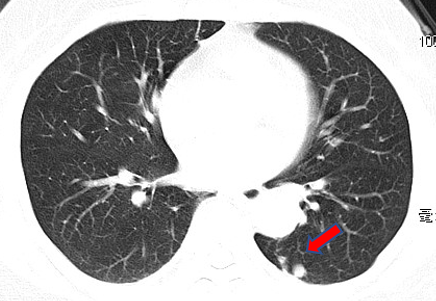

赵阿姨是一名普通的家庭妇女,年过半百,只求身体健康,能帮儿女带带孙辈。可是今年她莫名其妙开始咳嗽咳痰,一直不好,最近3个月还时不时发低烧。赵阿姨郁郁寡欢,儿女们急在心里,赶紧预约了医生。胸部CT吓人一跳:两肺有多发结节,赵阿姨乖乖吃了半个月的左氧氟沙星之后复查,没想到结节不仅没消失,反而逐渐增多了,一家人的心都悬了起来。

医生安排赵阿姨做支气管镜检查,病理初步排除了肿瘤的可能;又进一步做了国际上最先进的“微生物基因检测”(NGS),确诊赵阿姨为胞内分枝杆菌感染。医生说,这个菌是结核菌的兄弟、是“非结核分枝杆菌”大家族中的一员,没有传染性;治疗时间虽然比较长,但是可以防止肺功能变差,减少对寿命的影响。这下结节病因明确了,赵阿姨心中一块石头落了地。经过细致的治疗,赵阿姨现症状明显好转,重新投入到了带孙辈的“甜蜜的负担”之中。